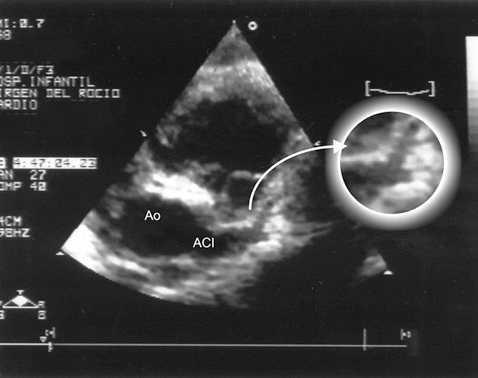

Fue tratado mediante ventilación mecánica, diuréticos e inotrópicos (dopamina, dobutamina y noradrenalina), y se añadió heparina tres días después, por aparición de un trombo apical en el ventrículo izquierdo (fig. 2), con lo que el paciente permanecía en situación crítica.

Figura 2. Trombo en el ápex del ventrículo izquierdo (13 días de vida): ecocardiografía 2D, proyección apical 4C. El trombo alojado en la región apical del ventrículo izquierdo tiene un diámetro de 1 cm.